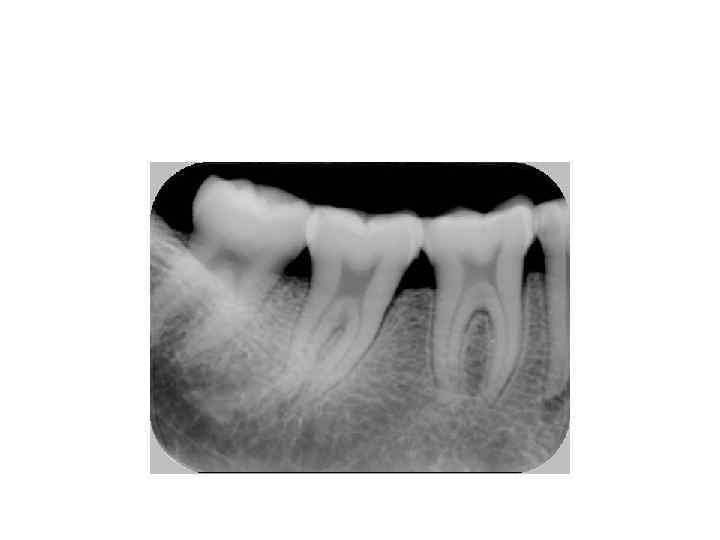

6. Имеют 2 корня. Крупнее и массивнее мезиальный корень. 7. Полость зуба повторяет форму коронки. Самый глубокий рог пульпарной камеры – вестибуло-мезиальный. 8. В мезиальном корне 2 канала, в дистальном 1 канал.